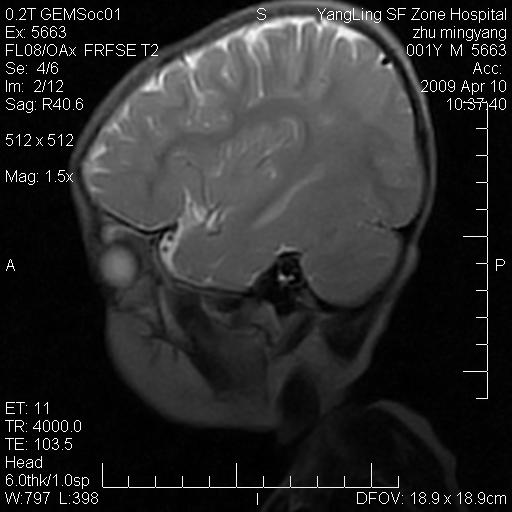

患者:1岁半,两天前外伤收住我院,ct检查小脑占位

考虑星形细胞瘤,建议增强

髓母细胞瘤或血管母细胞瘤,增强后可以鉴别;影像资料见 <。鱼博浪老师的《中枢神经系统ct与mr鉴别诊断》 小脑部肿瘤章节。

髓母细胞瘤或血管母细胞瘤!支持!

支持考虑髓母细胞瘤

考虑----髓母细胞瘤可能性大

考虑髓母细胞瘤或室管膜瘤。

支持髓母细胞瘤。

考虑髓母细胞瘤。

考虑髓母细胞瘤或星形细胞瘤

考虑髓母细胞瘤.

考虑髓母细胞瘤可能性大。

小脑肿瘤.考虑髓母细胞瘤可能.

就病灶部位及临床资料首先考虑髓母.